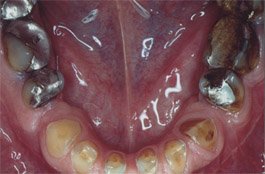

Die Folgen werden am Gebiss meist schnell sichtbar, denn langfristig führt das ständige Zähneknirschen zu Abnutzungserscheinungen an den Zähnen und zu Schäden und Schmerzen in den Kiefergelenken und Kaumuskeln (siehe Schmerzen im Bereich der Kaumuskulatur und Kiefergelenk-MAP).